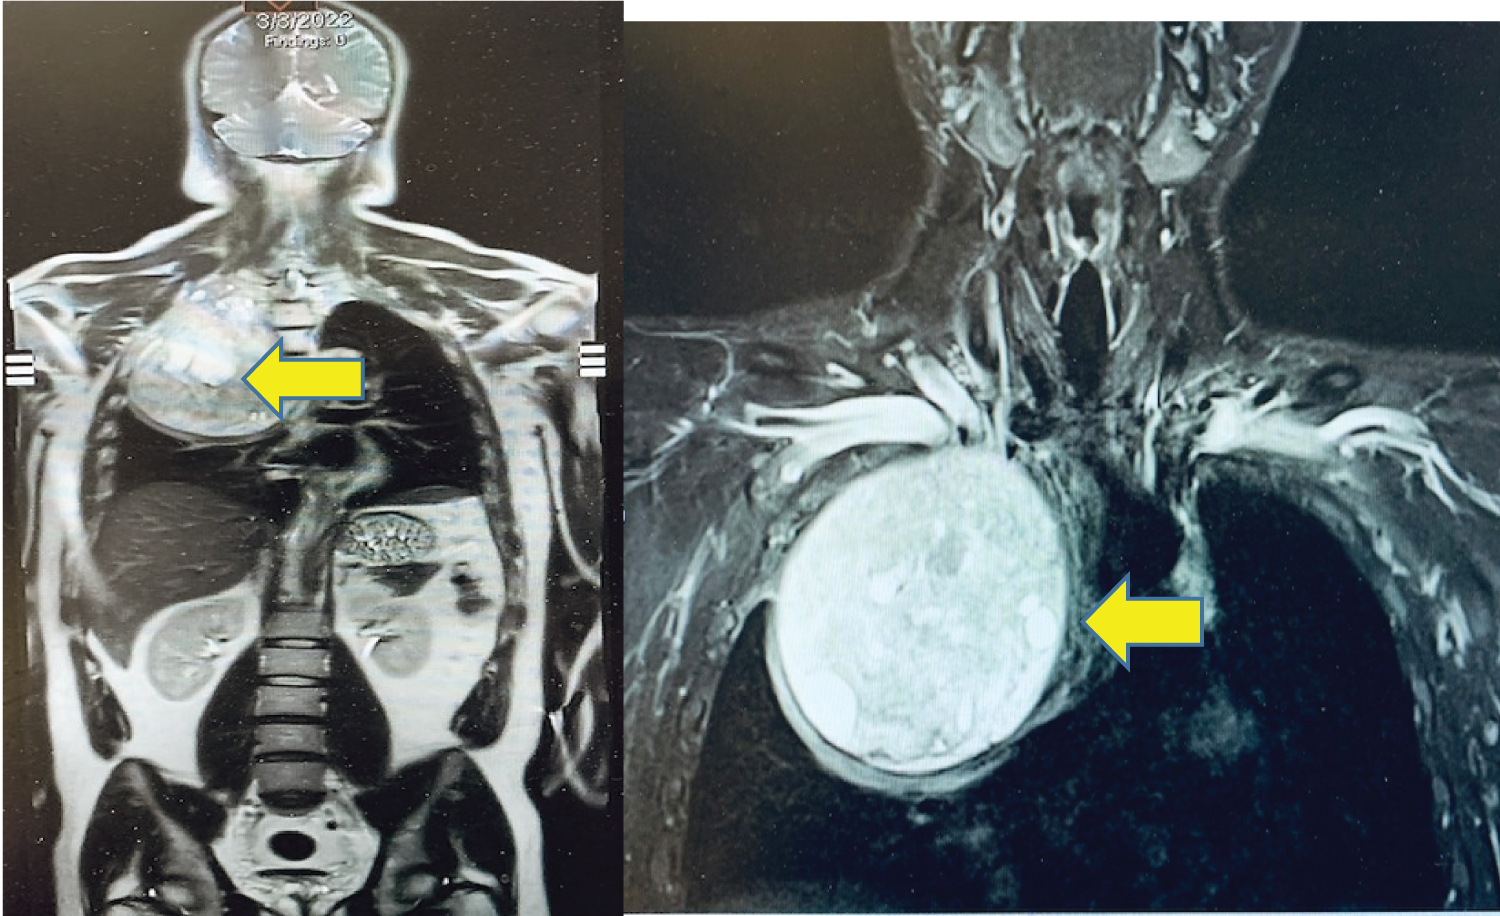

To start the case, the neurosurgeon placed the patient in the prone position to facilitate the dorsal approach to the right of T1-T4 spinous processes and corresponding vertebral bodies. At the level of T2 and T3, the transverse processes were transected, ribs disarticulated and the nerve roots ligated. The patient was then repositioned into the left decubitus position for the chest wall tumor resection including en bloc resection of a portion of T2 and T3 transverse processes (no reconstruction) (Figure 2).

Figure 2: En bloc resection of mesenchymal chondrosarcoma from inside of right chest.